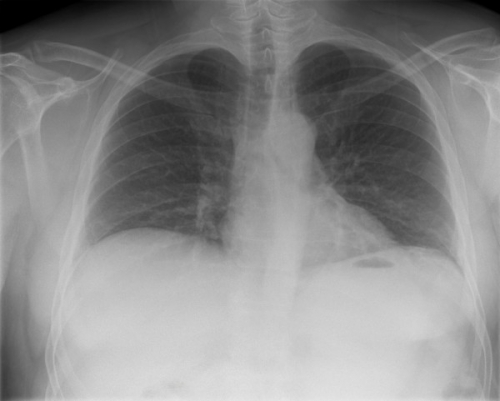

Tool to train medical student's eyes as to what a normal chest x-ray looks like, with over 500 consecutive normal images.